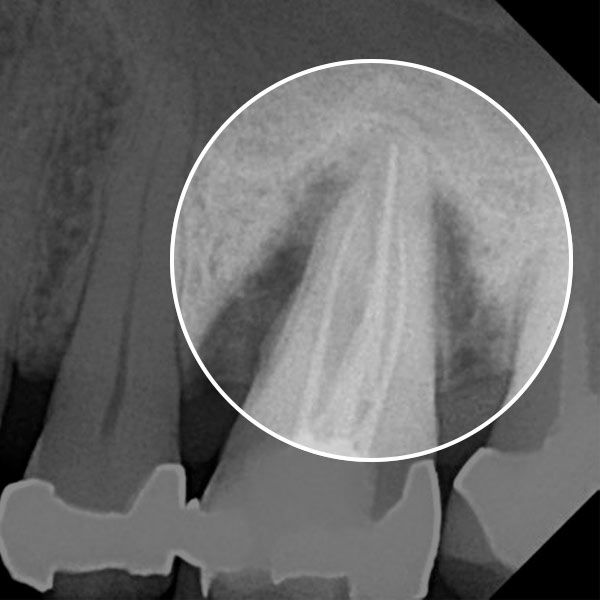

Before — Gum disease caused deep pockets to form.

After — The LANAP procedure restored a gum health.